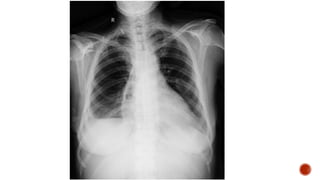

Frontal chest radiograph shows few ill defined patchy opacities in both the lung

fields, few of them showing cavitatory changes. TCC seen in situ.

Compared to the previous radiograph there is reduction in the number of opacities

with cavitatory changes.

 Malignancy:

 Squamous cell carcinoma of the lung

 Metastasis :

 squamous cell ca

 adenoca from GIT/breast

 sarcoma

 cervical carcinoma

 urothelial carcinoma of the bladder

 Infection :

 Septic embolism

 Pulmonary tuberculosis

 Abscess

 Post pneumonic pneumatocele

 Necrotizing pneumonia

 Autoimmune :

 Wegeners granulomatosis

 Rheumatoid nodules